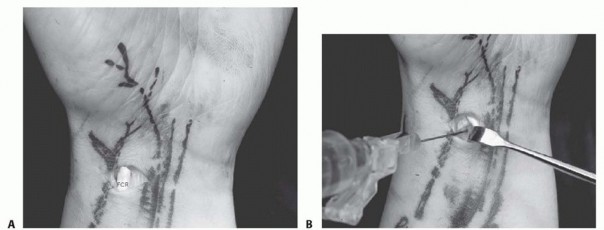

APPROACH

Portals are established by palpating and identifying anatomic landmarks and then inserting a 22-gauge needle into the joint space. The joint can be injected with 5 mL of saline. The ability to draw the saline back into the syringe serves as evidence that the needle is in the joint. This is not necessary for dry arthroscopy.Shallow incisions avoid injury to sensory nerve branches and tendons. Soft tissues are dissected using a blunt mosquito clamp or a pair of small tenotomy scissors. The dorsal capsule is pierced with these same instruments, providing access to the joint.A blunt trocar is used to introduce the scope cannula, which will house the scope and the inflow.An 18-gauge needle is placed in the 6U portal for outflow, but this is not needed with dry arthroscopy.Synovitis, fractures, ligament tears, and a tight wrist joint may limit the field of view and necessitate the use of more portalsto adequately assess the entire wrist.P.27

B. Saline injection of radiocarpal joint. C. Insertion of cannula through floor of the FCR sheath. (From Slutsky DJ. Volar portals in wrist arthroscopy. J Am Soc Surg Hand 2002;2:225-232.)